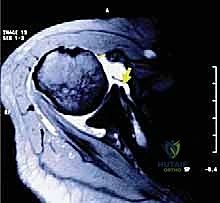

* الرنين المغناطيسي (MRI): المعيار الذهبي. يوضح بدقة حجم التمزق، تراجع الوتر، وجود ضمور دهني في العضلة، وحالة الأوتار الأخرى.

* الأشعة السينية (X-rays): لاستبعاد وجود كسور أو خشونة متقدمة في المفصل.